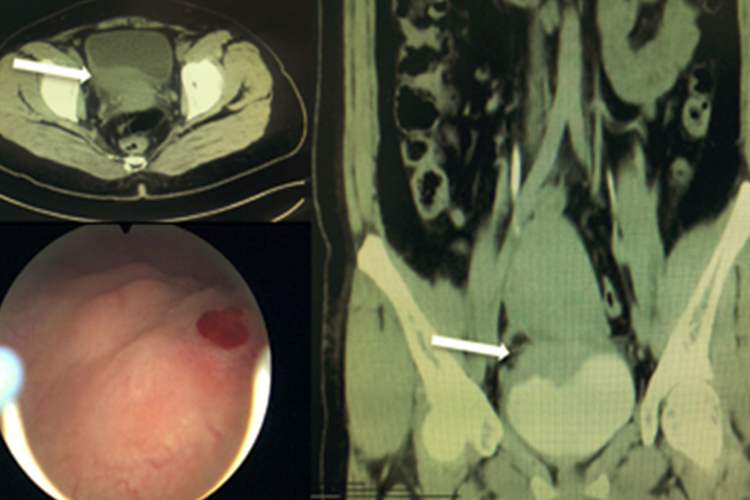

乳头状癌:单发或多发,肿瘤局限在黏膜或黏膜固有层,蒂细长,蒂上长出绒毛状分支,在膀胱内注水时,肿瘤乳头在水中飘荡,犹如水草;结节、团块乳头状癌蒂较粗,乳头分支短而粗,有时像杨梅状,往膀胱注水时活动较少,附近黏膜增厚、水肿。

浸润性癌:无蒂,境界不清,局部隆起,表面褐色或灰白色,肿瘤坏死处形成扁平的溃疡,溃疡出血或有灰白色脓苔样物沉淀,边缘隆起并向外翻,肿瘤附近黏膜不光洁、增厚、水肿、充血。